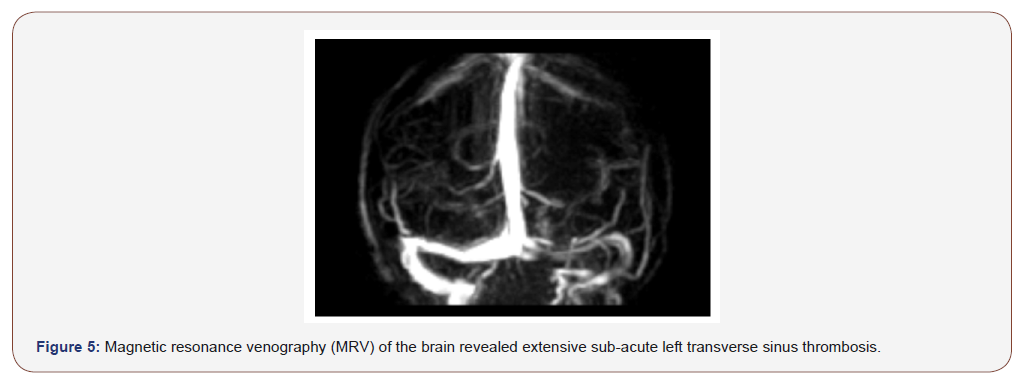

Contrast-enhanced brain magnetic resonance imaging revealed a left temporal and superior frontal subacute infarct (Figure 3), diffusion-weighted magnetic resonance imaging showed hyperintense diffusion restriction at the same area (Figure 4a and 4b). Magnetic resonance venography (MRV) of the brain revealed extensive sub-acute transverse sinus thrombosis (Figure 5). Doppler ultrasonography did not show any lesion on cervical arteries. Transthoracic and transesophageal cardiac ultrasound excluded thrombus or cardiac abnormalities.